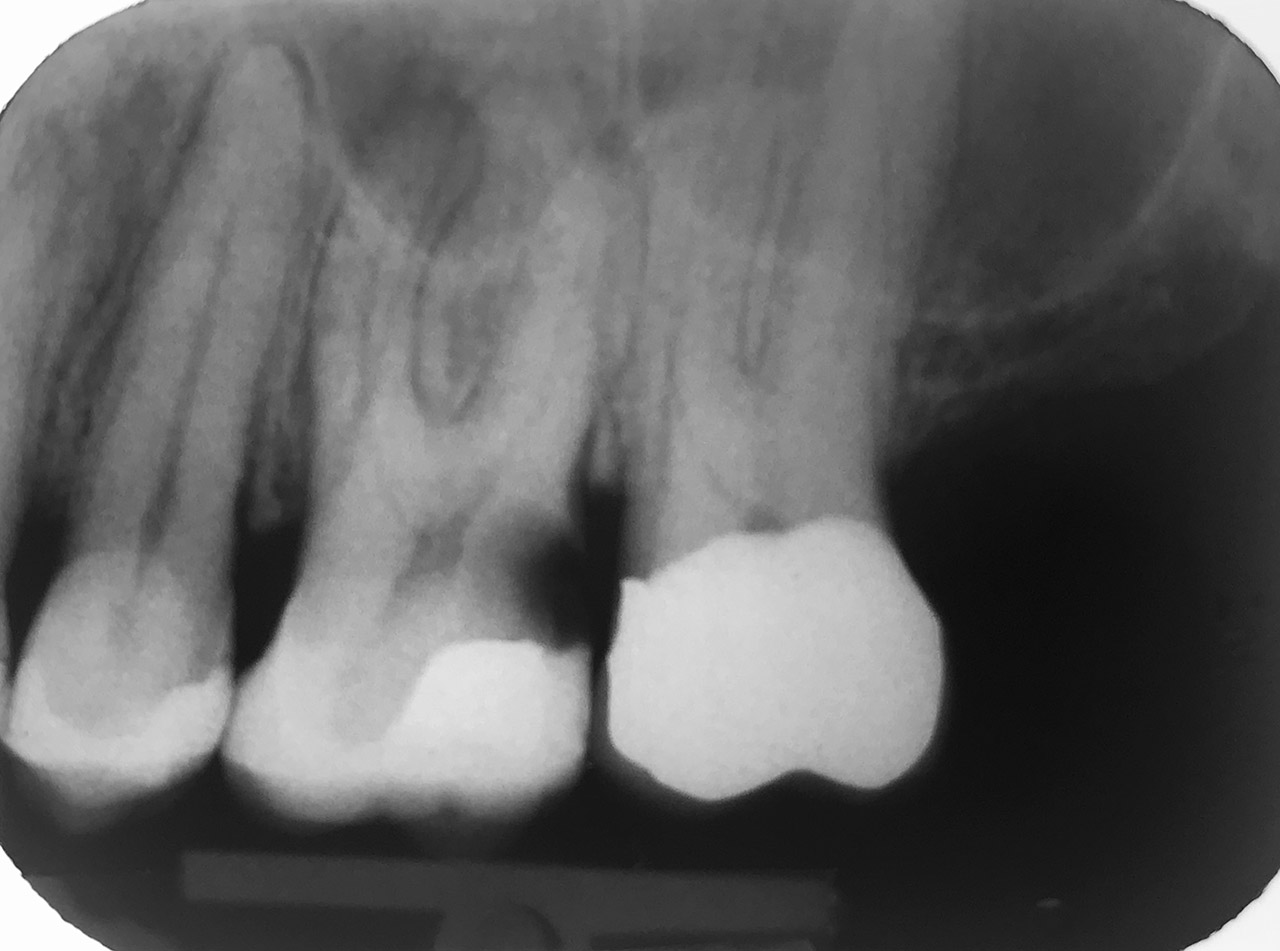

Endodontie/Wurzelbehandlung:

Befund: Aufbißschmerz und Schwellung auf Zahn 46. Frisch zementierte Krone (alio loco).

Therapie: Abnahme der Krone, Entfernung der Zementreste, Revision der insuffizienten Wurzelbehandlung.

Glasfaserstifte und neue Krone, beides adhäsiv zementiert.